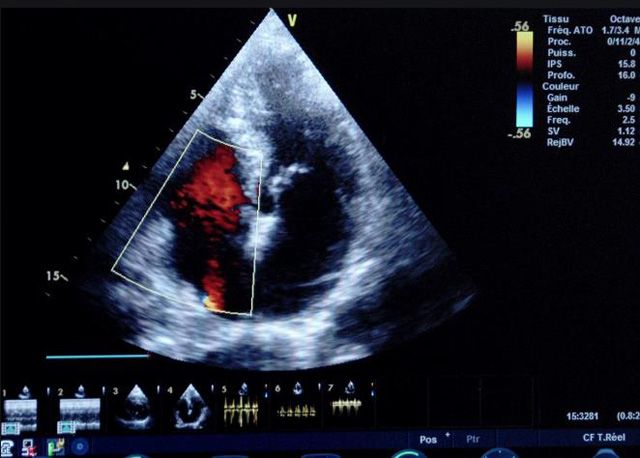

二、彩色室壁運動分析

(一)基本原理彩色室璧運動分析,從整體散射數據中識別心內膜邊界,並與前一幀彩色不同,心髒收縮或舒張期開始到結束時心內膜的全部過程。每一次順序顯示結束後,原來的彩色自動消失,以便進入下一個顯示過程。其結果是獲得對應於每一個心動周期的彩色顯示,描繪特定周期內室壁運動的時間運動軌跡。

(二)操作步驟根據背向散射數據中將心內膜運動的位移過程分類為組織或血液的原理,邊緣檢測跟蹤心內膜和血液的界麵。橙色表示收縮期的開始,收縮期不同時相逐幀顯示色彩均疊加在收縮末期最後一幀圖像中。檢查時,可按以下步驟進行:

①顯示較為理想的二維圖像,常用切麵有心尖四腔心、二腔心、左心室長軸和左心室乳頭肌水平短軸切麵。

③啟動CK係統,啟動後劃定感興趣區域。同時記錄的心動圖R波頂點為舒張末期,T波終點為收縮末期,顯示RT間期的CK彩階圖,連續記錄3~ 5個心動周期。